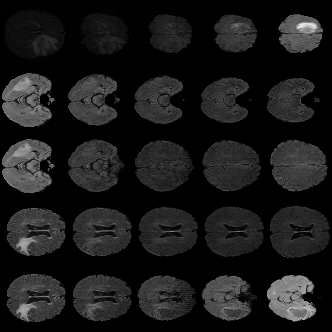

Disentangled representations can be useful in many downstream tasks, help to make deep learning models more interpretable, and allow for control over features of synthetically generated images that can be useful in training other models that require a large number of labelled or unlabelled data. Recently, flow-based generative models have been proposed to generate realistic images by directly modeling the data distribution with invertible functions. In this work, we propose a new flow-based generative model framework, named GLOWin, that is end-to-end invertible and able to learn disentangled representations. Feature disentanglement is achieved by factorizing the latent space into components such that each component learns the representation for one generative factor. Comprehensive experiments have been conducted to evaluate the proposed method on a public brain tumor MR dataset. Quantitative and qualitative results suggest that the proposed method is effective in disentangling the features from complex medical images.